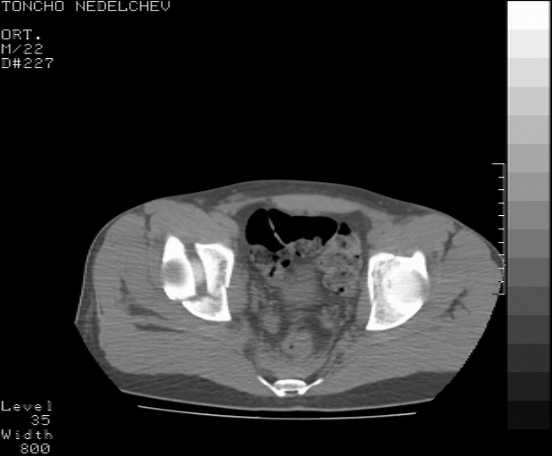

Re: Acetabular fracture

Here are some more axial images. What is your opinion as for the timing of the operative treatment?